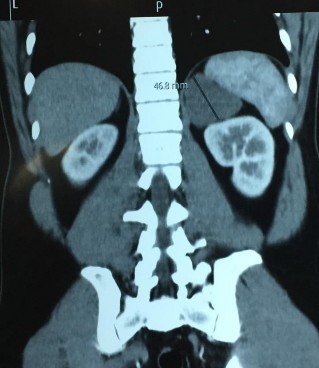

Phim CT scan bướu TTT bên trái, không chức năng

[Hồ Đình D., 32 tuổi, SNV: 214114642]

Bệnh phẩm bướu hạch thần kinh bên trái